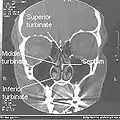

- Normal Nose CT Front cross section